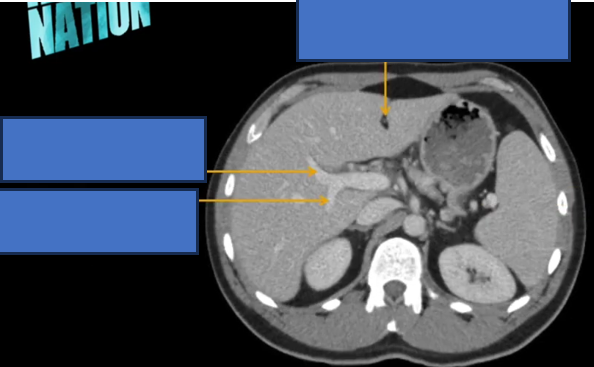

TM gan ở đâu? TM chủ dưới ? ĐM chủ?